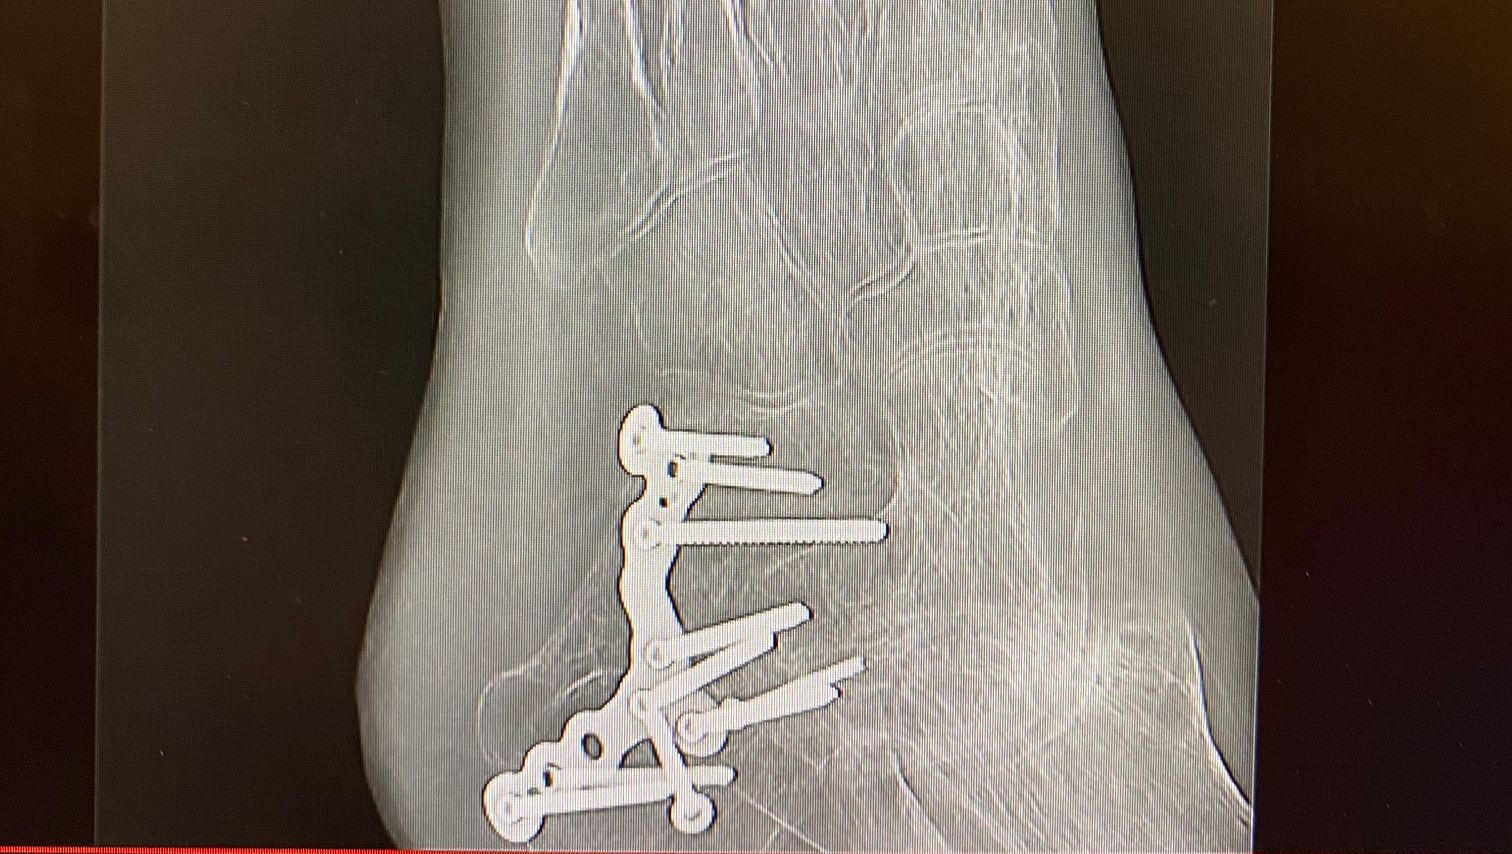

On that scary day, he landed directly on the calcaneus bone in his left heel, which was crushed like an eggshell. He was rushed to the hospital for emergency surgery.

They installed 10 screws and a metal plate to repair the broken bones, but he developed a rare nerve disease called Complex Regional Pain Syndrome Type II, also referred to as Causalgia.